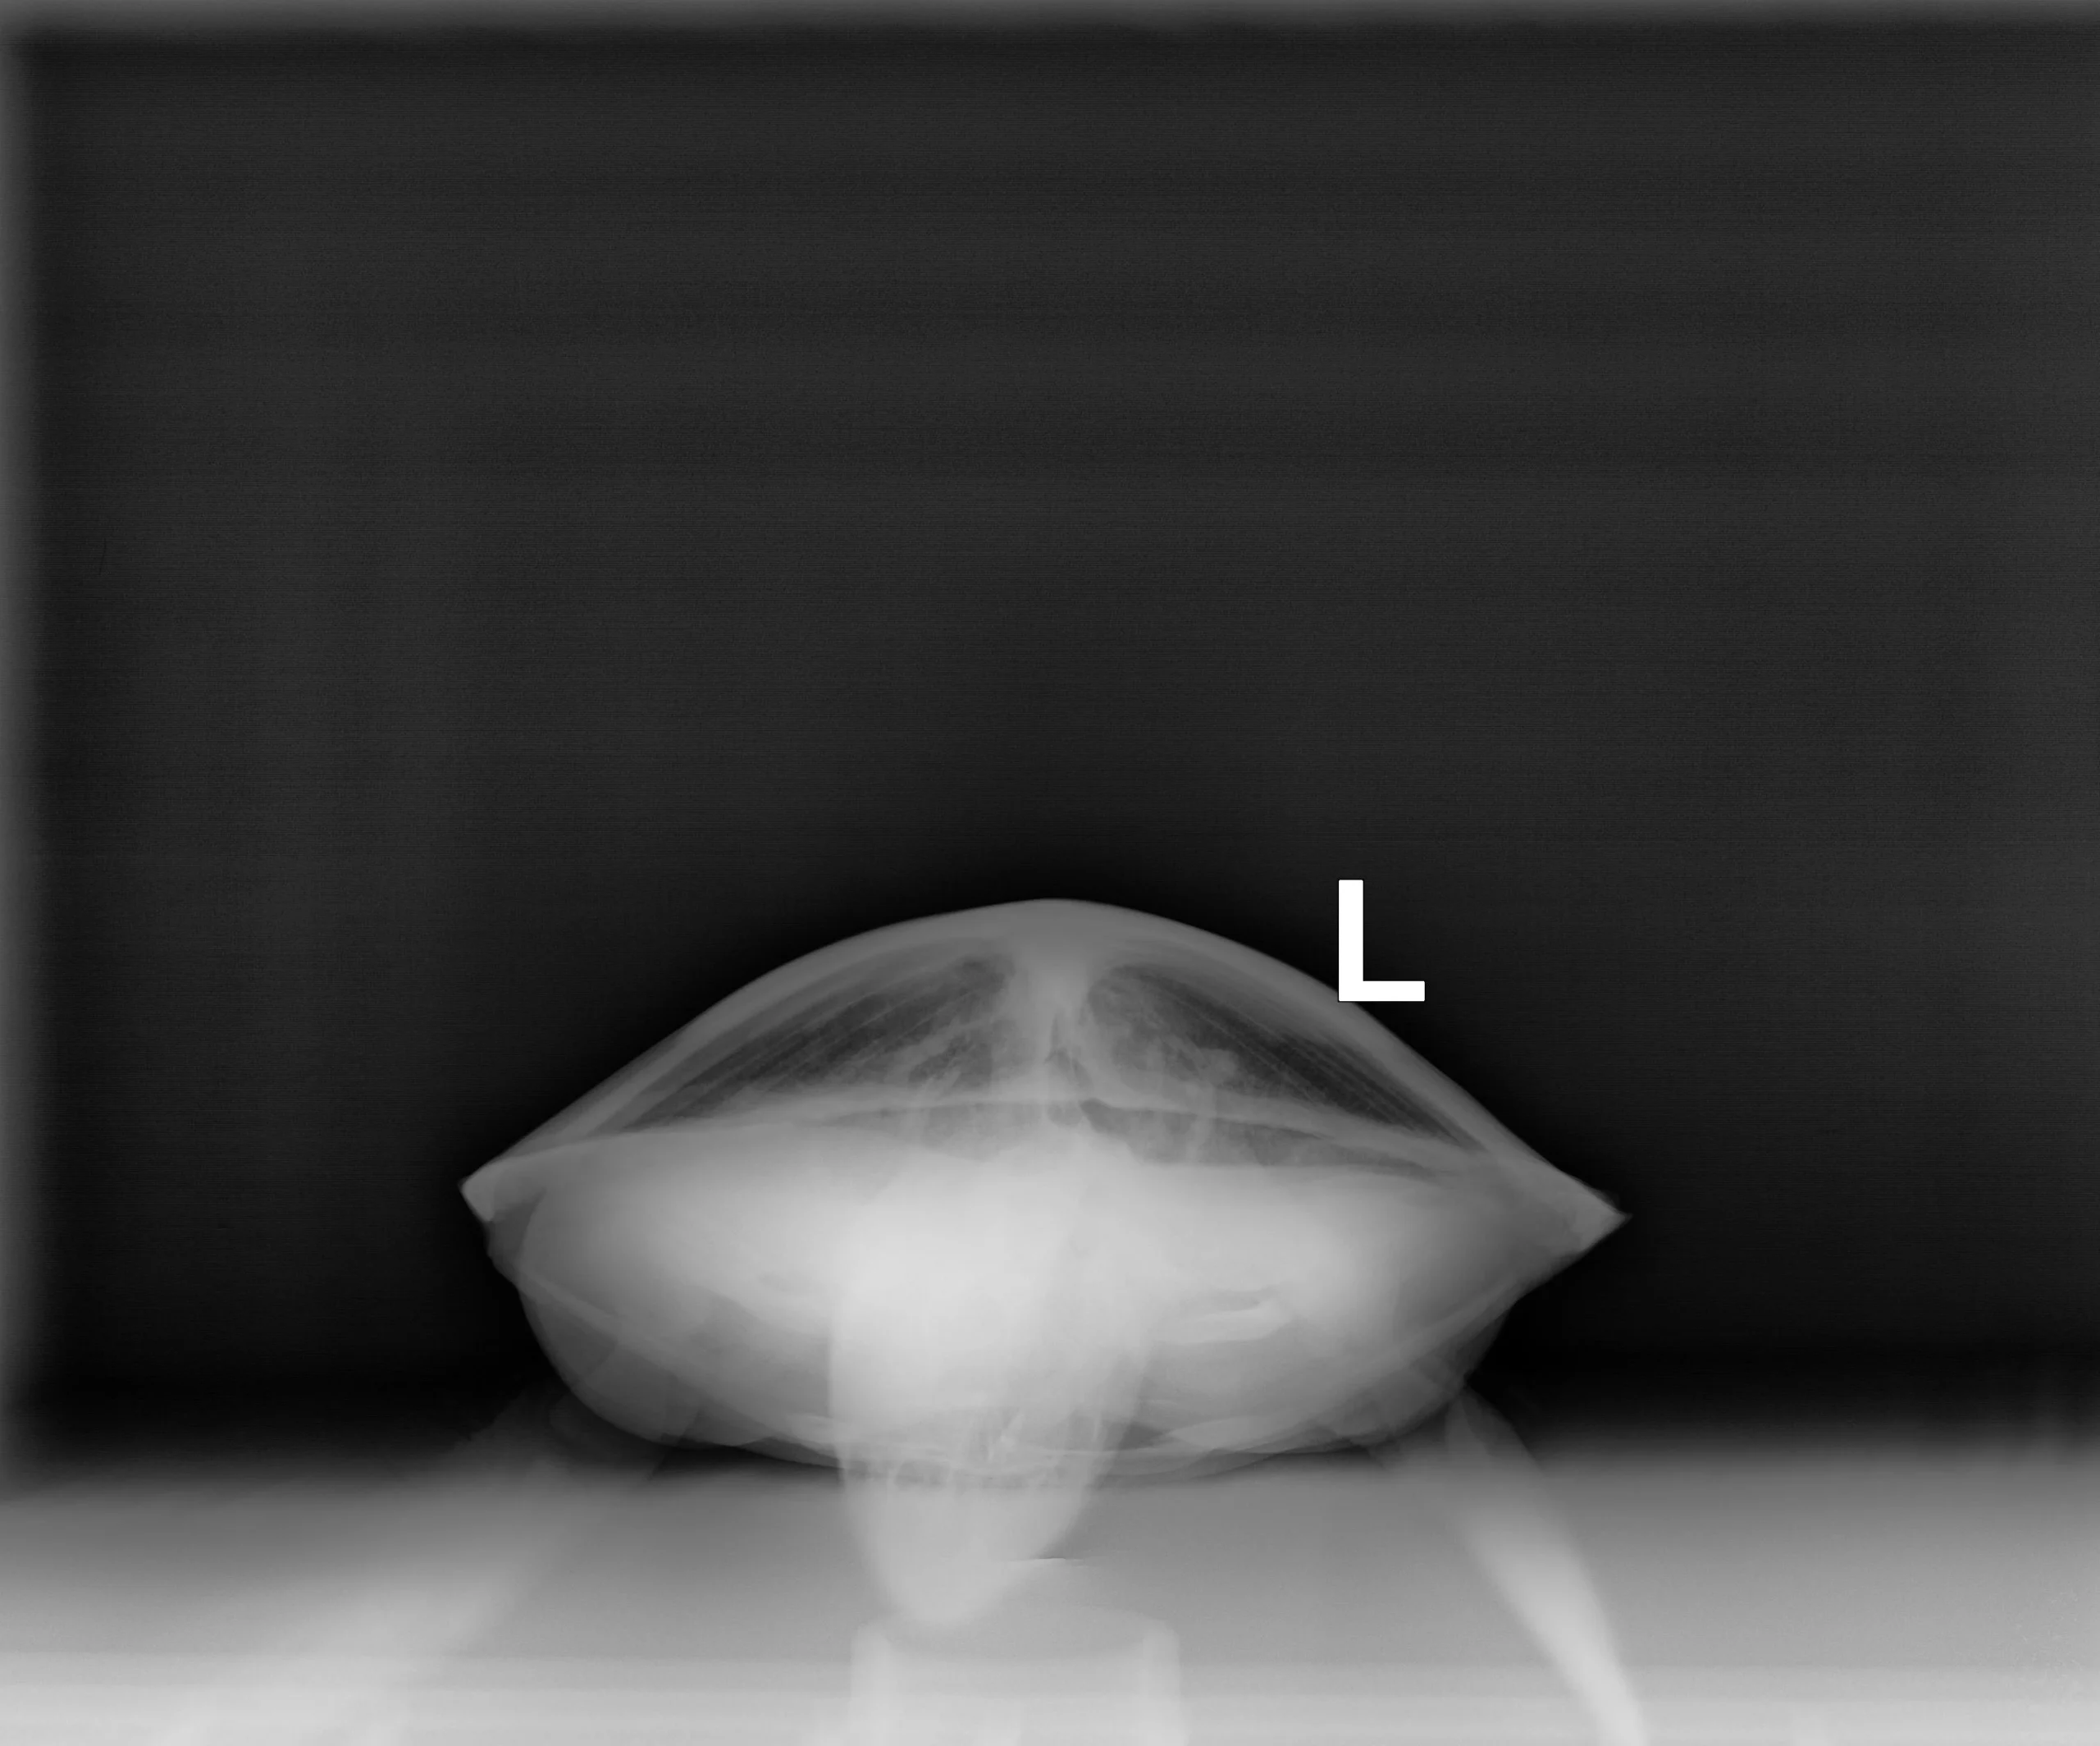

2.05 kg juvenile Atlantic Green sea turtle

Patient Injuries

External Carapace Notes: Minor abrasions, old healed fracture to the upper right side carapace, abrasions on the left side marginal scutes on carapace

Plastron: Minor plastron abrasions

External Wounds: old healed fracture to the upper right side carapace